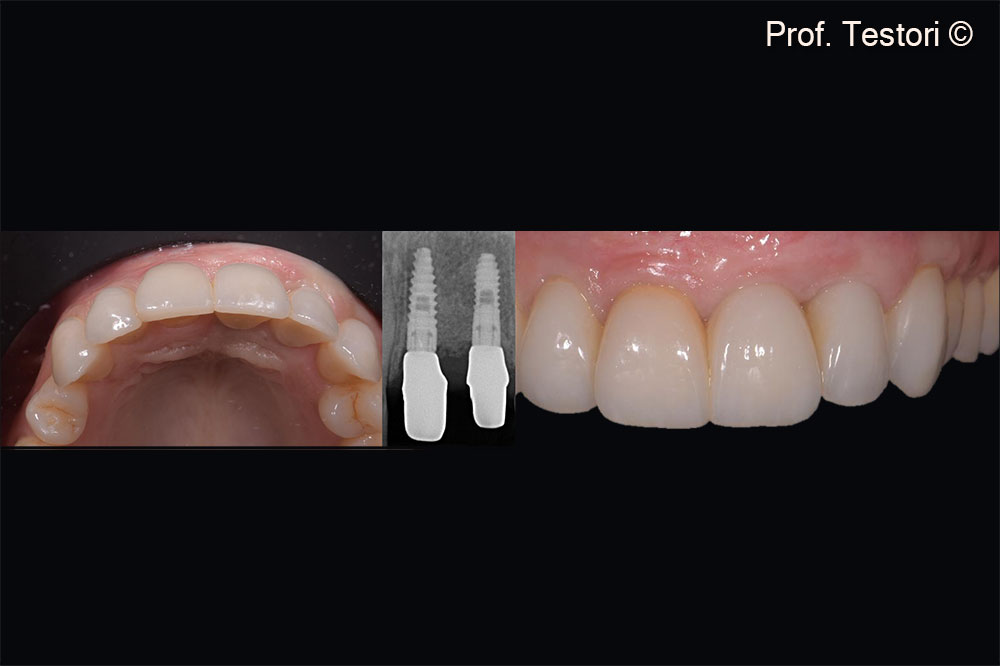

Implants are firmly anchored to newly formed bone. No signs of peri-implantitis are detected

5-year follow up. Implants are firmly anchored to newly formed bone. No signs of peri-implantitis are detected.